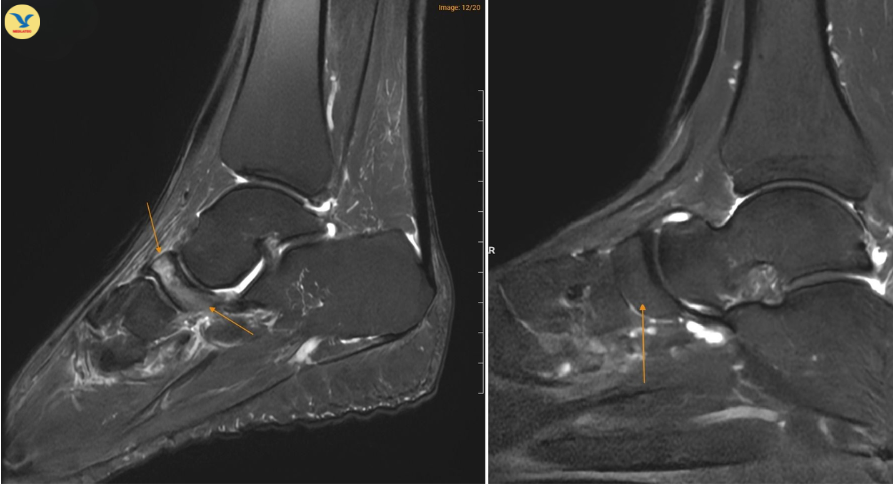

MRI chân trái ghi nhận hình ảnh thoái hóa khớp và phù nề

Đồng thời ghi nhận hình ảnh tổn thương gai xương thoái hóa khớp cổ chân trái, ổ phù tủy xương vị trí xương sên, phù nề dây chằng chày mác sau, dây chằng sên mác sau, dây chằng gót chày và dây chằng tam giác cổ chân, dịch khớp cổ chân, phù nề phần mềm quanh khớp cổ chân.

Dựa trên sự phối hợp chặt chẽ giữa lâm sàng và chẩn đoán hình ảnh, chị H. được chẩn đoán theo dõi Hội chứng Muller-Weiss phải, phù tủy xương sên trái.